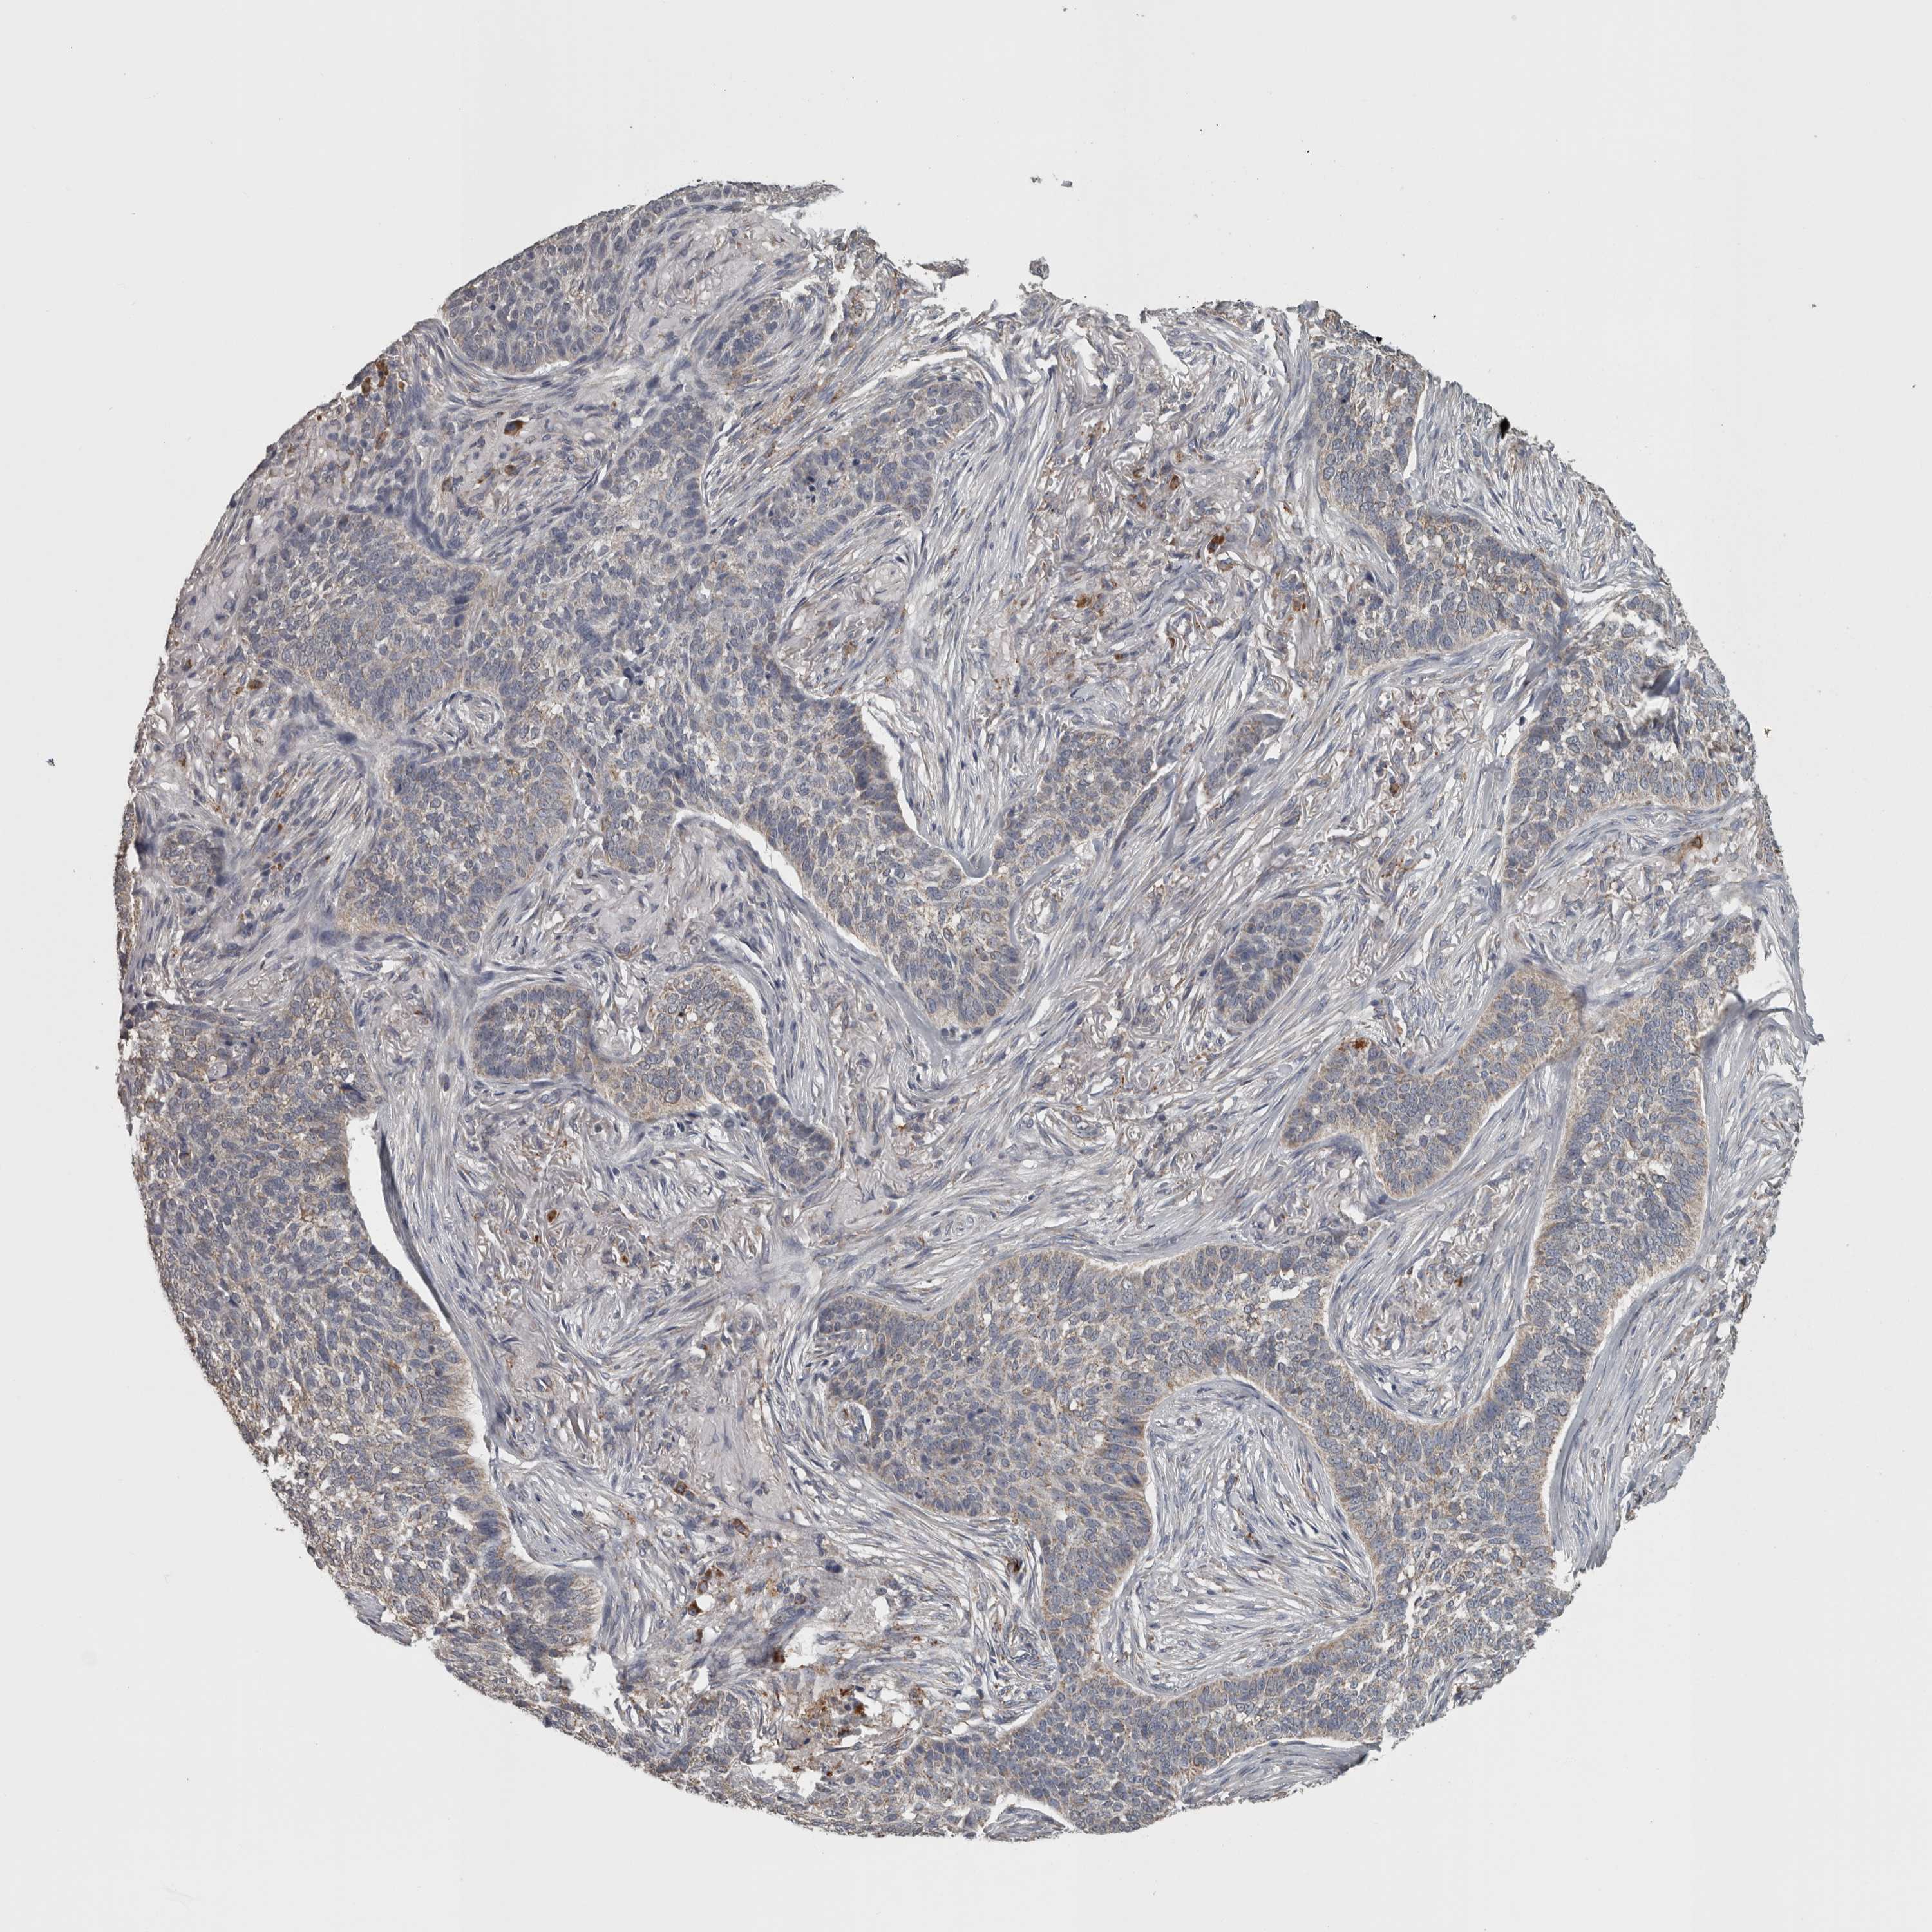

Basal cell and squamous cell cancer

SKIN CANCER - Protein expressioni

A mouse-over function shows sample information and annotation data. Click on an image to view it in a full screen mode. Samples can be filtered based on level of antibody staining by selecting one or several of the following categories: high, medium, low and not detected. The assay and annotation is described here.

Antibody stainingi

Antibody staining in the annotated cell types in the current human tissue is reported as not detected, low, medium, or high, based on conventional immunohistochemistry profiling in selected tissues. This score is based on the combination of the staining intensity and fraction of stained cells.

Each image is clickable and will lead to virtual microscopy that enables deeper exploration of all samples and also displays staining intensity scores, fraction scores and subcellular localization as well as patient and tissue information for each sample.

Antibody HPA072590

Staining

High

Medium

Low

Not detected

Intensity

Strong

Moderate

Weak

Negative

Quantity

>75%

75%-25%

<25%

None

Location

Nuclear

Cytoplasmic/membranous

Cytoplasmic/membranous,nuclear

Basal cell carcinoma